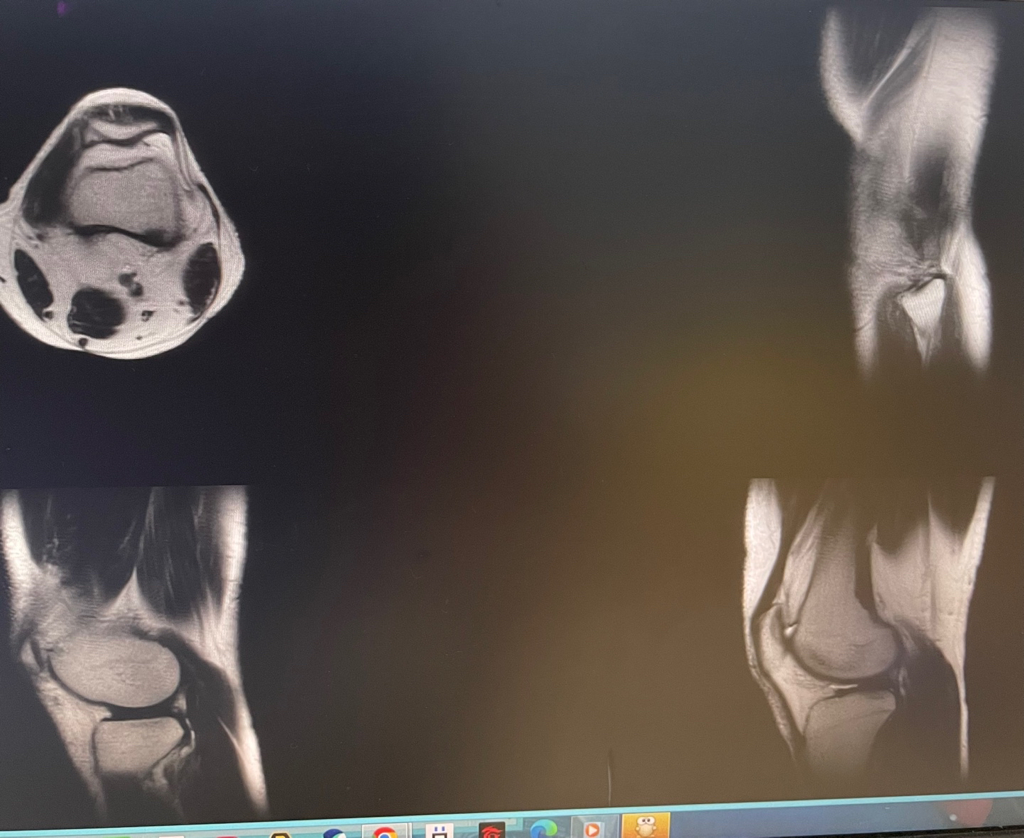

무릎이 너무 자주 아파서 mri를 찍어봤는데 무릎 연골에 이상이 있을까요

무릎이 선천적으로 원형연골인지 봐주시면 감사하겠습니다

• 2번 째 사진

MRI 판독에는 퇴행성 연골 손상, 바깥쪽 원판형 반월상 연골 이 의심된다고 적혀 있습니다.